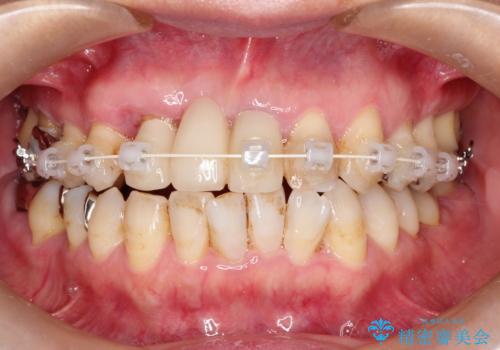

矯正を併用した前歯のセラミックブリッジ治療

- 上顎前歯をきれいにしたいとのことで来院されました。

レントゲンを撮影すると保存が難しい歯がありました。

またがたつきの度合いから歯を1本抜歯して矯正治療を行いセラミックブリッジを装着することで、審美的・機能的改善を行う計画としました。

治療の順序は

①保存不可の歯の抜歯・根管治療

②矯正治療

③セラミックの装着

という流れで行いました。

1年程度の治療期間が必要となりましたが、仕上がりには患者様に満足していただけました。